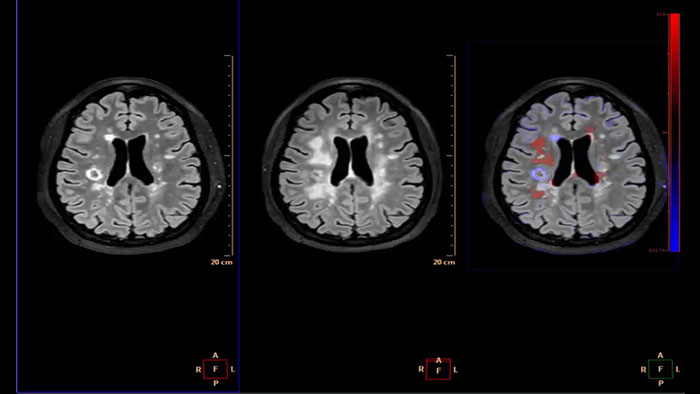

Generates qualitative and quantitative information about changes in image intensity over time. The application calculates and displays quantitative color maps of cerebral blood flow (CBF), cerebral blood volume (CBV), mean transit time (MTT) and time-to-peak (TTP), and provides summary maps which may help physicians in determining areas of reduced cerebral blood flow compared to the contra lateral hemisphere.

Reviewing brain tissue perfusion viability

Provides physicians with supporting information for the evaluation of stroke, or assessment and follow-up of brain tumors. The application supports the analysis of T2* Perfusion studies to generate parametric data including TTP, MTT or Tmax.